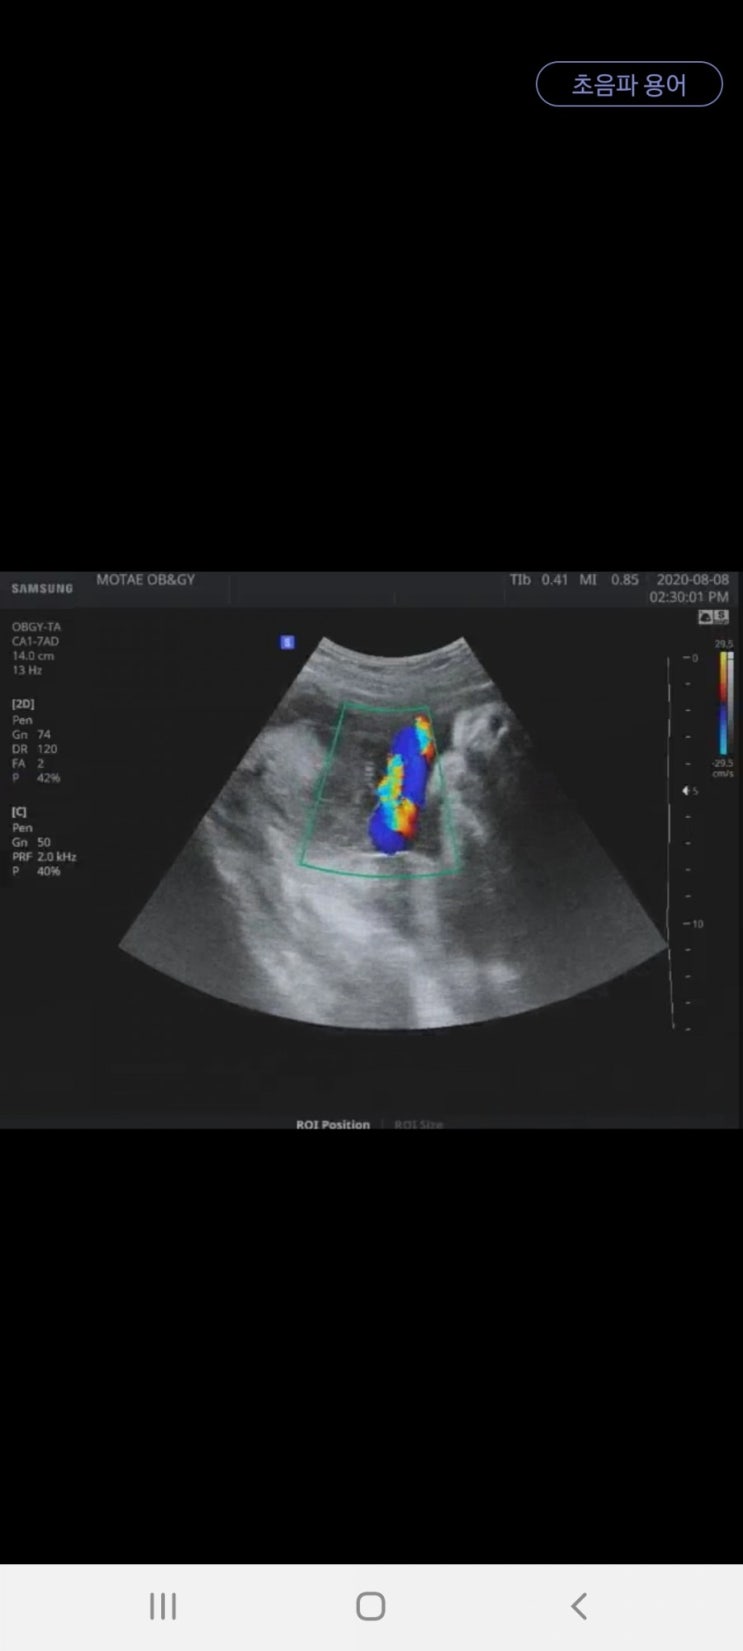

예비 달이맘_임신부터 출산 story_39주차_정기검진 다녀왔어요~수축검사 및 내진

2020.8.8 Sat 39주 1일차에 접어들었답니다! 어느새 39주...사실 39주가 되기전에 우리 달이가 나와줬으면...